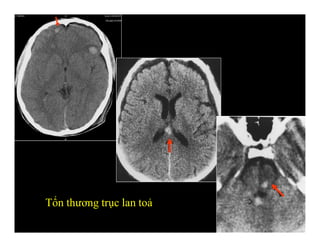

TỔN THƯƠNG TRỤC LAN TOẢ

(Diffuse axonal injure/ Shear injury)

-Thường hình ảnhCT bình thường -Hoặc biểu hiện các nốt chảy máu nhỏ, rải rác -Vị trí : vùng ranh giới chất trắng-xám bán cầu, thể chai, cuống não sau-bên -MRI có giá trị trong chẩn đoán TỔN THƯƠNG TRỤC LAN TOẢ (Diffuse axonal injure/ Shear injury)